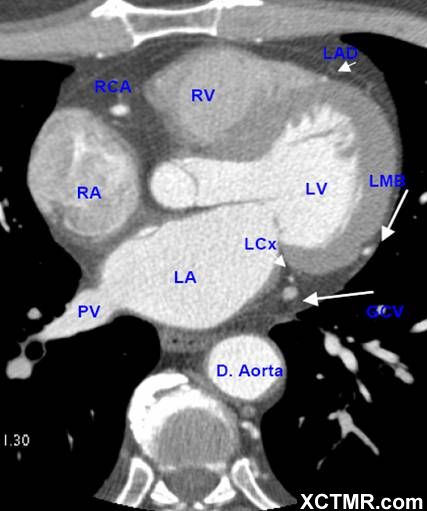

LA - Left Atrium 左心房

RA - Right Atrium 右心房

LV - Left Ventricle 左心室

RV - Right Ventricle 右心室

D. Aorta-Descending Aorta 降主动脉

PV - Pulmonary Vein 肺静脉

LAD - Left Anterior Descending Artery 左前降支

LCX - Left Circumflex Artery 左回旋支

LMB - Left Obtuse Marginal Branch 左边缘支(钝缘支)

RCA - Right Coronary Artery 右冠状动脉

GCV –Great Cardiac Vein 心大静脉